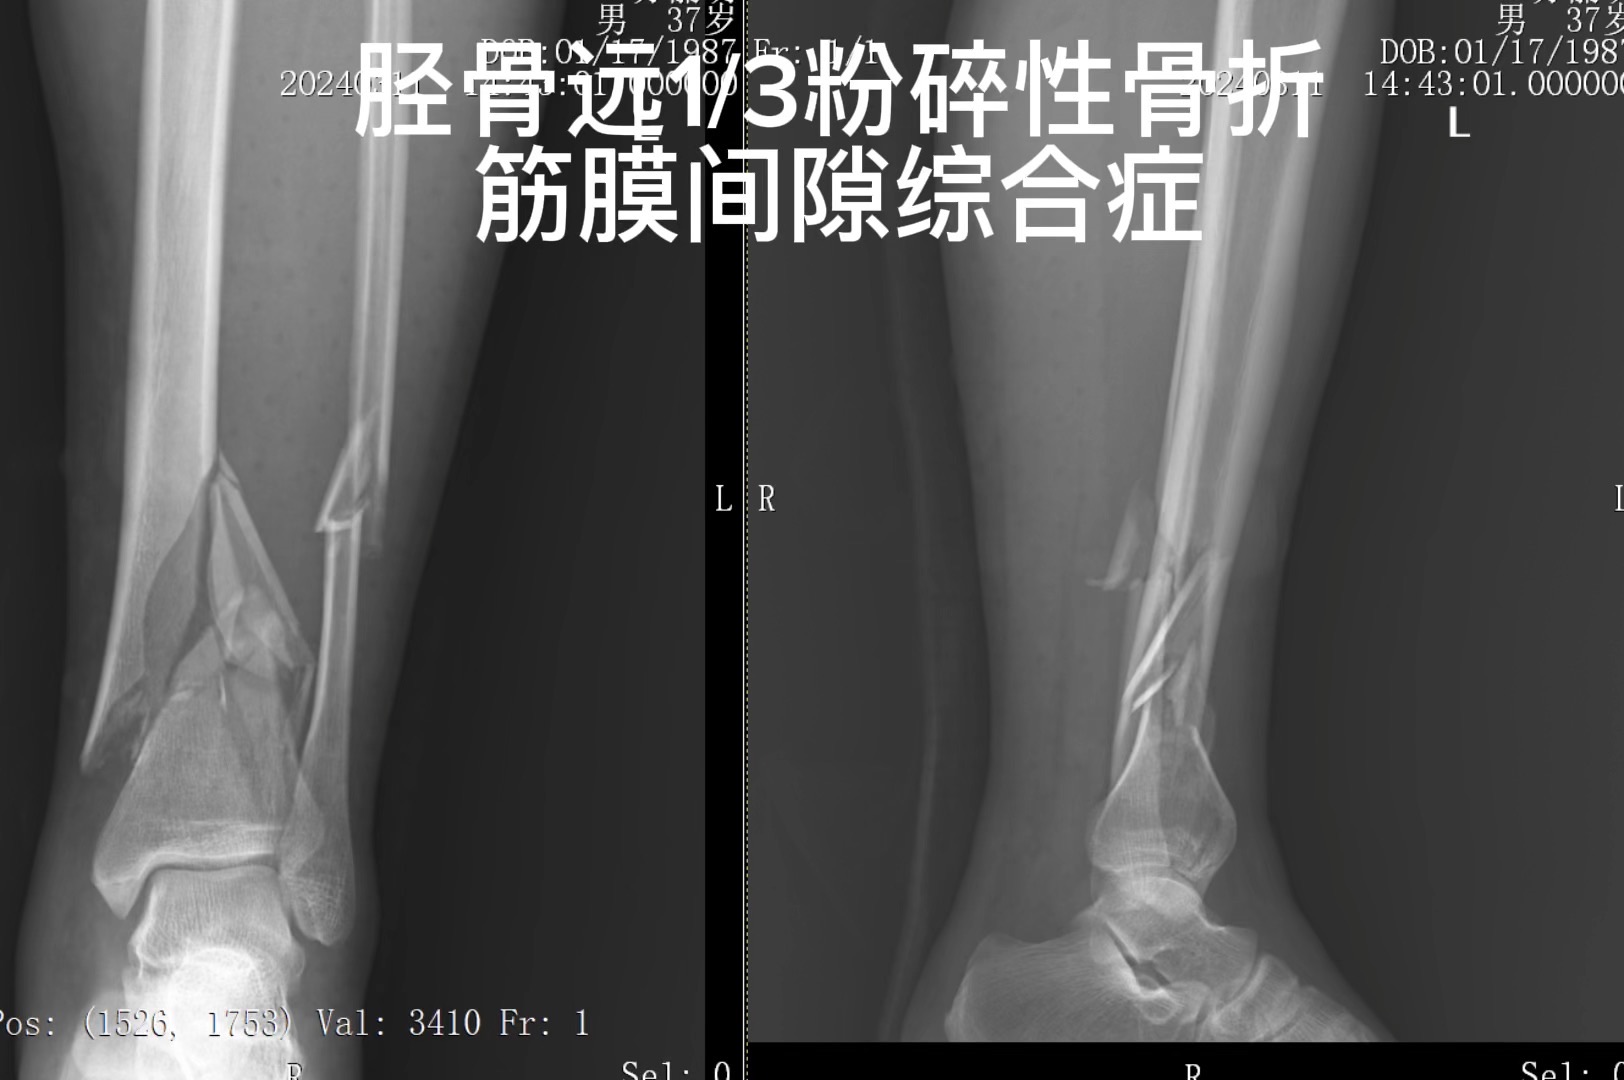

胫腓骨下段粉碎性骨折并筋膜间隙综合症 微创能做到什么程度

左胫腓骨CT结果显示:

左胫腓骨下段粉碎性骨折

左胫骨内踝及外踝骨折

左小腿及踝关节周围软组织肿胀

根据患者车祸外伤史,结合专科查体及辅助检查结果,确诊为

左胫腓骨下段粉碎性骨折。

筋膜间隙综合症